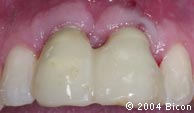

78. | 就位的一体化基台冠的颊侧观。 |